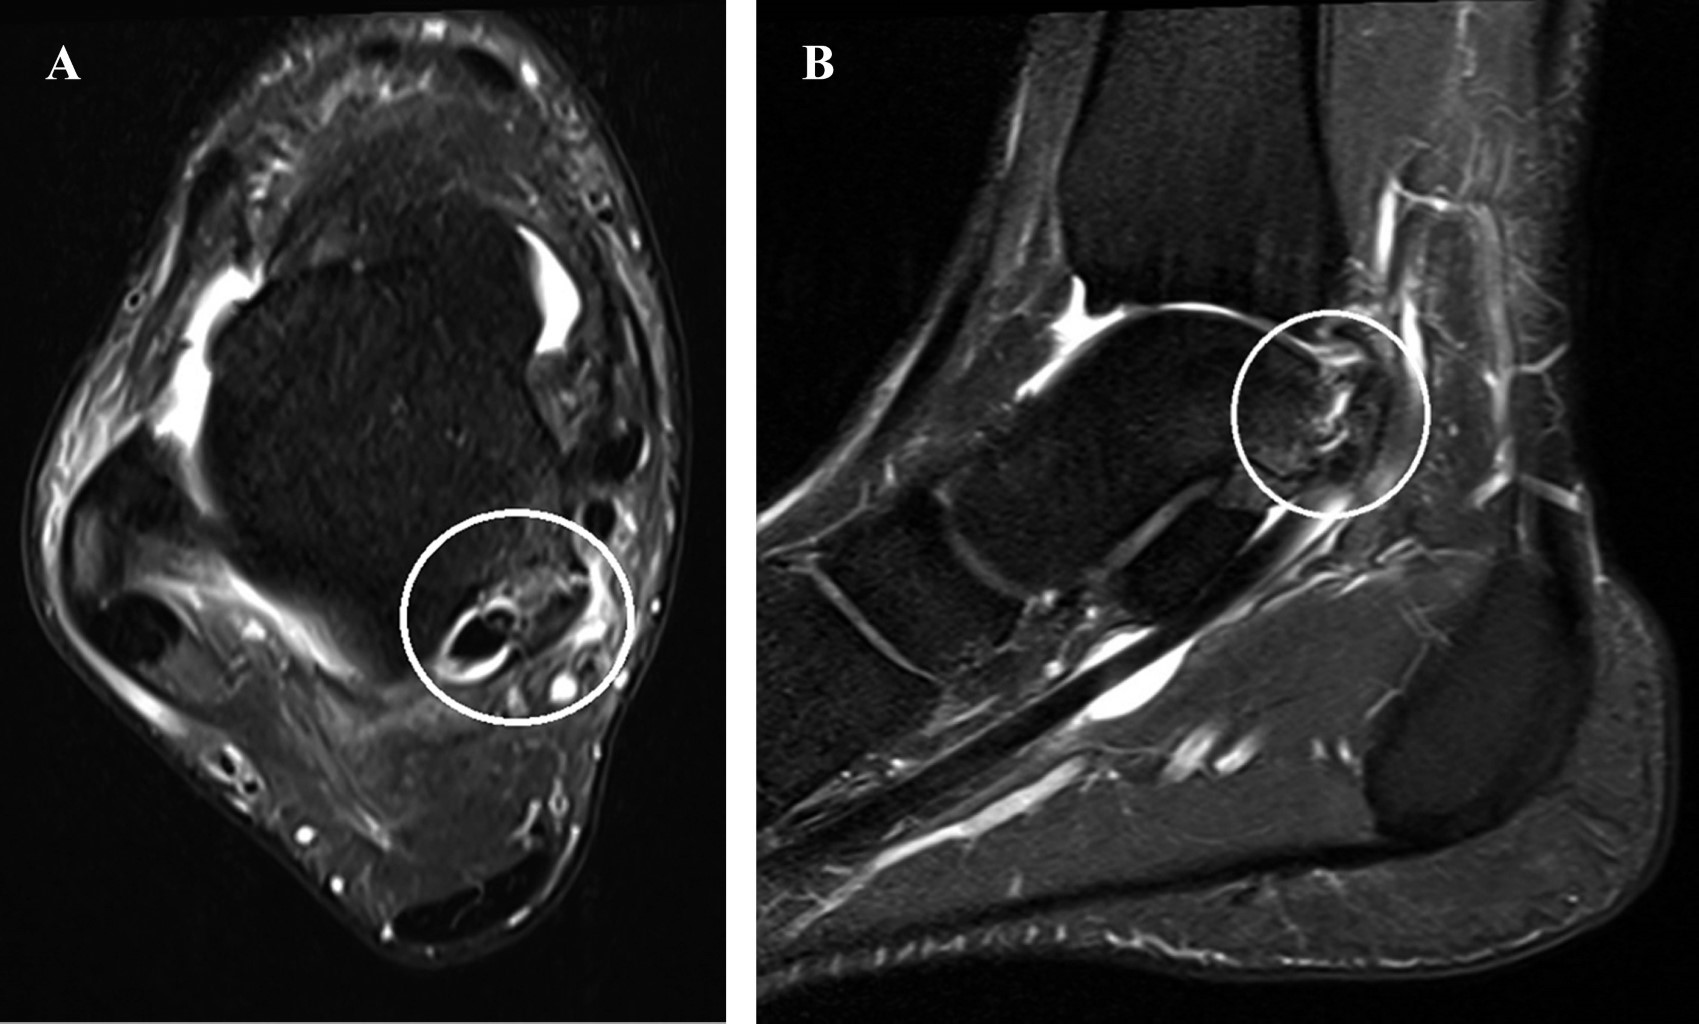

Fractura del tubérculo medial de la apófisis posterior del astrágalo en un jugador de fútbol rápido. Una fractura poco frecuente tratada con éxito de forma conservadora

El astrágalo es el segundo hueso más grande en la región posterior del pie y participa en las articulaciones talocrural (tobillo), subtalar y talonavicular. Las fracturas del astrágalo representan solo el uno por ciento de todas las fracturas de pies y tobillos, siendo la fractura del tubérculo medial del proceso posterior del astrágalo una lesión poco común, causada por la ruptura del ligamento talotibial posterior después de la dorsiflexión y la pronación traumática. Tales fracturas pueden no ser evidentes radiográficamente, como se describe en este caso raro de fractura del tubérculo medial del proceso posterior del astrágalo con un resultado satisfactorio sin necesidad de tratamiento quirúrgico.

Figura 1